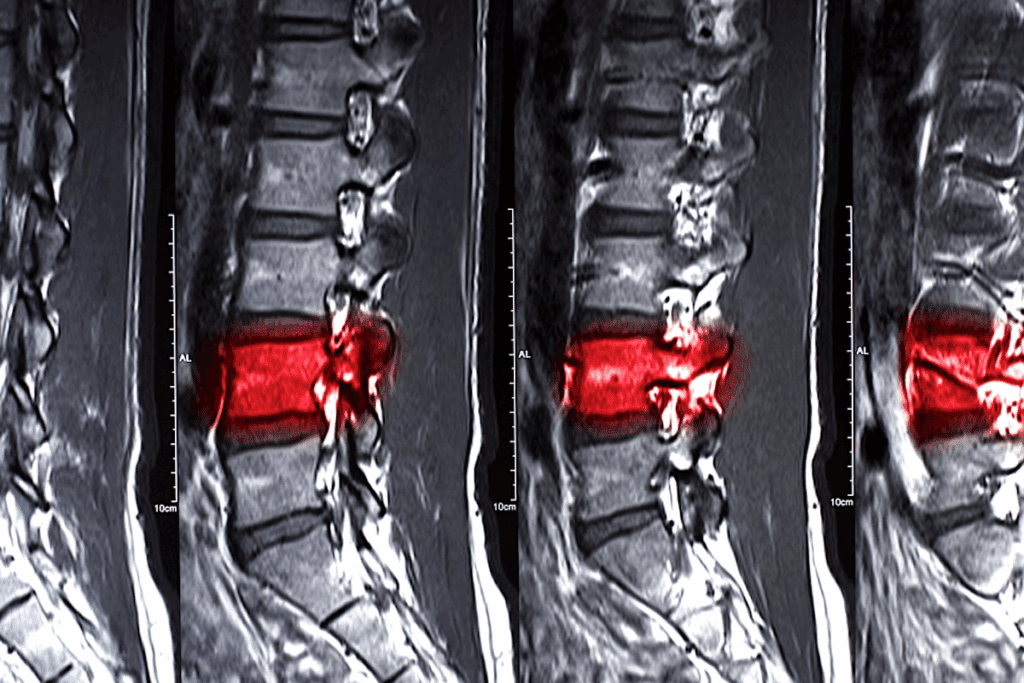

Diagnostic Approaches

Diagnosing L5 S1 conditions involves physical exams, patient history, and imaging. MRI scans are very helpful. They show detailed images of soft tissues like discs and nerves.

Healthcare providers check muscle strength and pain during physical exams. This helps find the problem’s source. Knowing this is key for creating a good treatment plan, whether it’s l5 s1 disk protrusion treatment or other methods.